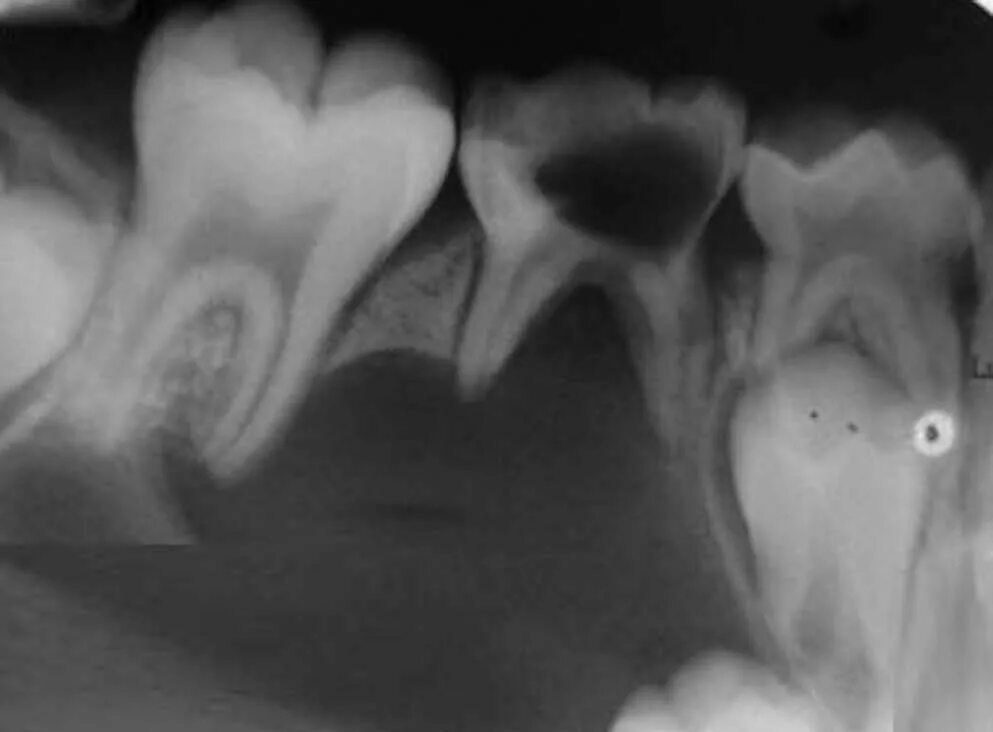

Киста зуба что это